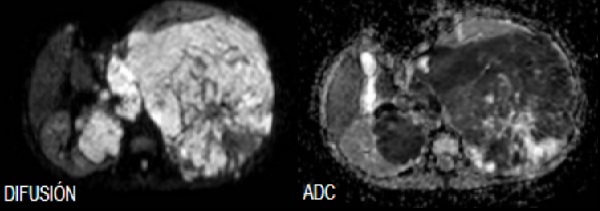

5. RMN Abdomen con contraste:

RMN: Masa retroperitoneal hipointensa en T1, realce heterogéneo con el contraste.

Hiperintensa en T2. Restringe en su mayor proporción y áreas que no restringen en relación

con áreas de necrosis.